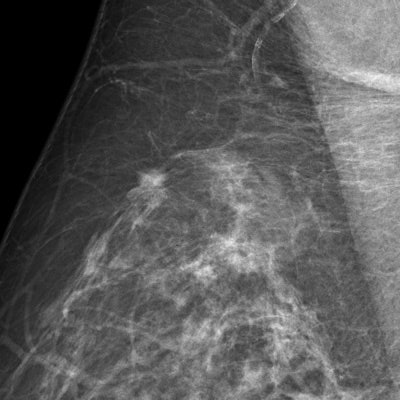

"Traditional CAD doesn't take into account risk factors such as age or genetics. This combined with its 98% sensitivity for finding microcalcifications means that the radiologist must decide whether or not the often numerous findings are clinically relevant," said Bick, who presented an update on breast CAD at today's session.

![A 68-year-old asymptomatic woman underwent routine mammographic screening (above). A subtle small spiculated mass was correctly detected by CAD in the upper-outer quadrant of the right breast, best seen on the mediolateral oblique (MLO) view (below). Percutaneous biopsy and subsequent surgical excision confirmed a 10-mm well-differentiated, lymph-node-negative invasive ductal cancer in the right breast [pT1b pN0 (sn) G1], which had an excellent prognosis due to its early detection through mammography screening. Images courtesy of Dr. Ulrich Bick.](https://img.auntminnie.com/files/base/smg/all/image/2015/03/am.2015_03_06_00_09_16_89_2015_03_06_CAD3.png?auto=format%2Ccompress&fit=max&q=70&w=400)

Results from the European breast cancer diagnosis project, HAMAM, which uses CAD in a more patient-tailored approach, are promising. The project integrates MRI, mammography, and ultrasound with risk factors such as age and gene mutation carrier information. Some risk factors, such as breast density and composition, can even be extracted and factored into CAD's findings.

"For example, CAD could distinguish that four calcifications clustered together in a young patient with dense breasts are more likely to be relevant than in a 70-year-old with low-density fatty breasts," Bick noted. "At present the commercial application of CAD is in pure detection. However, the research points to integrating different modalities, risk factors, and detection into a clinical decision aid."

For the moment, some of CAD's advantages are clear-cut: e.g., finding microcalcifications is tedious for the reader, as the image needs to be checked in quadrants due to resolution issues. CAD, however, speeds up the process by looking at the full image in full resolution and pointing to these microcalcifications. This frees up the human reader to concentrate on other areas such as density, masses and architectural distortions for which the computer is less trained. However, with CAD's average of one false prompt per case, time still risks being wasted on recalls, which in a screening program should not exceed 5% for a human reader.